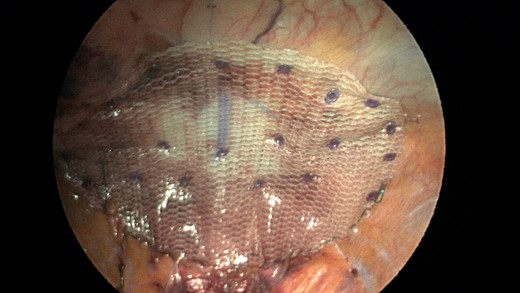

Completed view of the second main mesh piece placed with overlap of the defect and tack fixation in place.

Additionally, another Pariatex composite mesh was then trimmed to 12 cm in width by 9 cm, soaked in vancomycin with local anesthetic and then placed into the abdominal cavity. It was positioned over the area of the repair and fixed into place with absorbable tacks around its caudad edge and centrally. Along the cephalad edge it was fixed with a running V-lock absorbable suture to the diaphragm. Fibrin glue was placed along this same edge (Fig. 7). The ports were removed and incisions were closed.